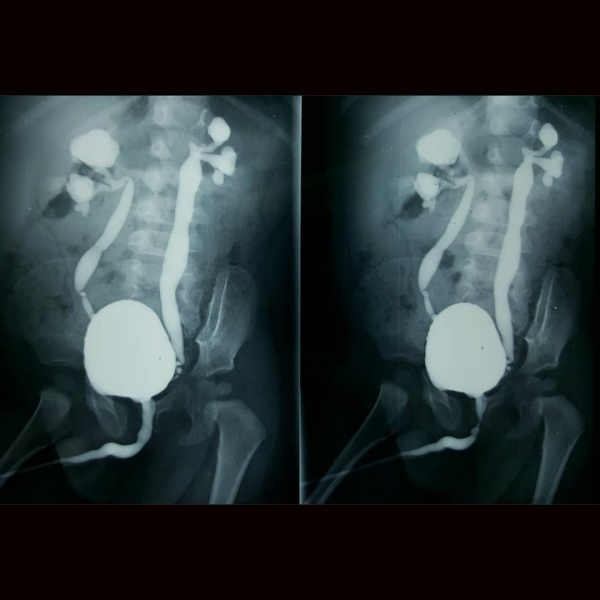

Uretrocistografia miccional. 877862 Idime

IDIME. Instituto de Diagnóstico Médico. Código de Convenio : 8915

BOGOTÁ

Sede Norte: Autopista Norte No. 122 – 68

BUCARAMANGA

Carrera 27 No. 30 - 15 Segundo Piso Hospital Universitario Los Comuneros

INCLUYE MEDIO DE CONTRASTE